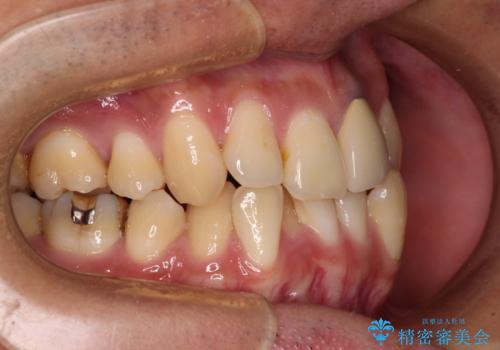

- 下顎の八重歯を気にして来院された患者様です。

左下以外、3本の第一小臼歯が既に抜去されており、左下は八重歯になっている状態でした。

左下の八重歯は手前に傾斜していたため、インビザラインによる抜歯矯正が可能と判断し、後方にある第一小臼歯を抜歯してインビザラインにて矯正治療を行うこととしました。